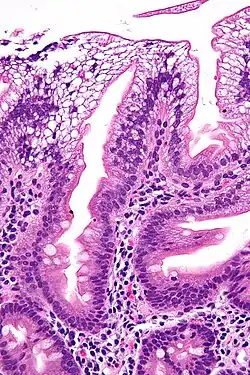

- gestörte Fettaufnahme aus dem Dünndarm mit Steatorrhoe

- Malabsorptionssyndrom